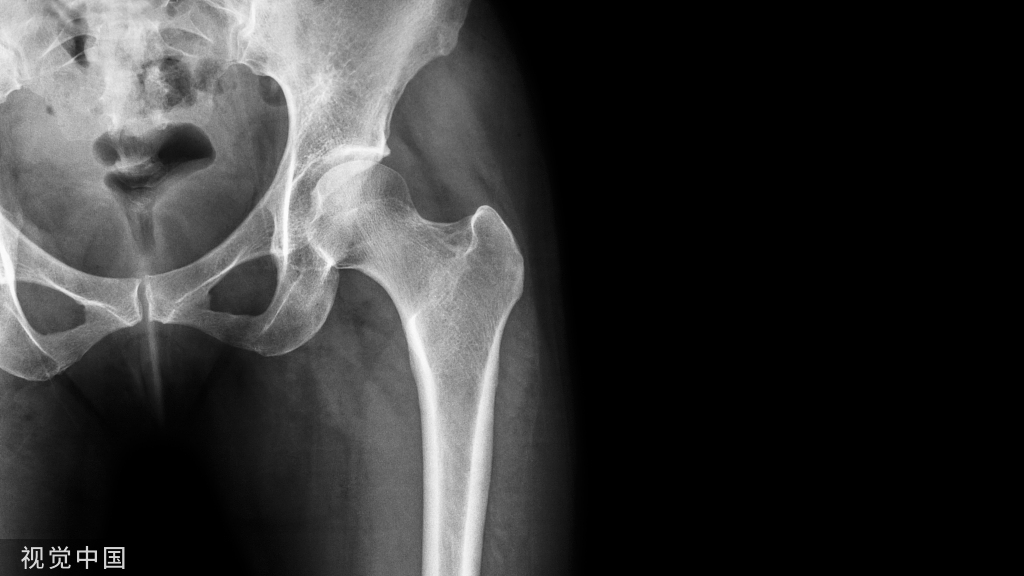

▲ 中1/3锁骨骨折患者,行切开复位内固定术,重建钢板安置于锁骨上表面,术前(A)及术后(B)X线片